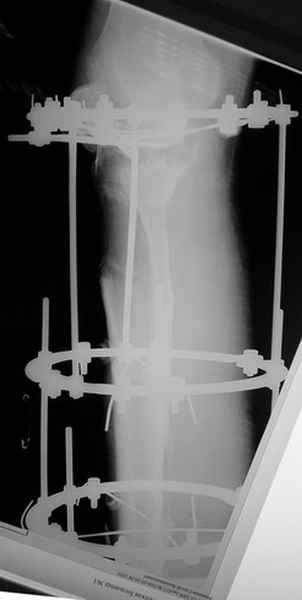

Пациент В. 53 лет, травма в феврале 2009. ДЗ. Открытый оскольчатый перелом нижней трети голени. При боли поступлении выполено ПХО, аппарат Илизарова. В последующем проводили ВХО, резекция костных отломков, укорочение 6 см, рана зажила. Была выполнена остеотомия большеберцовой кости в проксимальном отделе, резекция. Производилось тракция. На последних рентгенограммах выявлено, что одновременно с "выращиванием" регенерата произошло низведение надколенника на длину выращенного регенерата. Клинически: активное разгибание сохранено, объем движений в колене 180-110 градусов. Черными стрелками обозначен верхний край надколенника с одной и с другой стороны. Красная стрелка обозначает пальпируемую связку надколенника. Причина - остеотомия выше места прикрепления связки надколенника. Вопрос: была ли у кого подобная ситуация? Что делать? При первом обдумывании приходит решение: отсечение места прикрепления связки надколенника с костным блоком, перемещение на "правильное" место, укорочение сухожилия четырехглавой мышцы.

Я бы уменьшил диастаз между фрагментами сантиметра на два. Судя по снимкам, регенерат это может позволить.

Чтобы не сталкиваться с таким осложнением, лучше удлинять большеберцовую кость на уровне диафиза. Тогда еще и интрамедуллярный стержень будет удобнее вводить по завершении удлинения ;-)